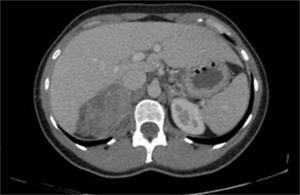

Se realizó tomografía computada que evidenció una lesión suprarrenal derecha quística, lobulada, de 97 por 59 por 87 mm (figura 1).

Figura 1: Tomografía computada.

Si bien se describen algunas características tomográficas (lesión sólida, bien definida, pudiendo ser lobulada, hipodensa, encapsulada y hasta en un 40% a 60% tener calcificaciones), al igual que en la resonancia magnética (hipointensos en T1 y heterogéneos e hiperintensos en T2) en general no son patognomócos1.